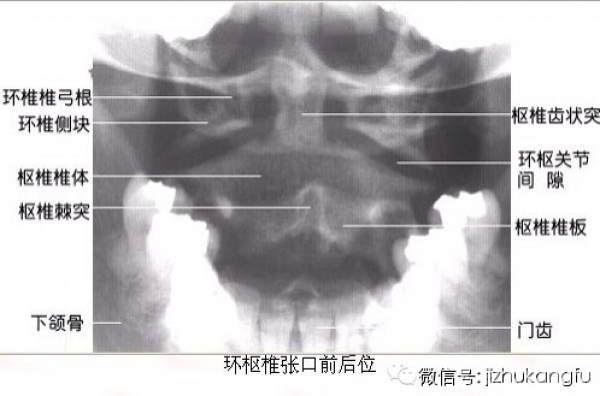

1寰枢椎的判读